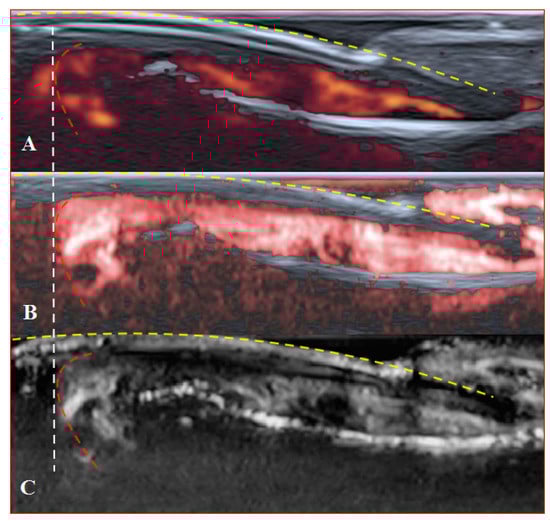

Figure 6. Sagittal scans of a healthy fingertip with high gain: (A) PD; (B) cSMI; (C) mSMI. The true flow is the highest signal that dissociates from the random noise dots clearly. It is hard to say how much blooming artefact is involved. The transverse dotted line through all images separates the area under the nail close to the fingertip (red dotted line); a gel manicure does not change the quality of the image but longer nails provoke flash artefacts.